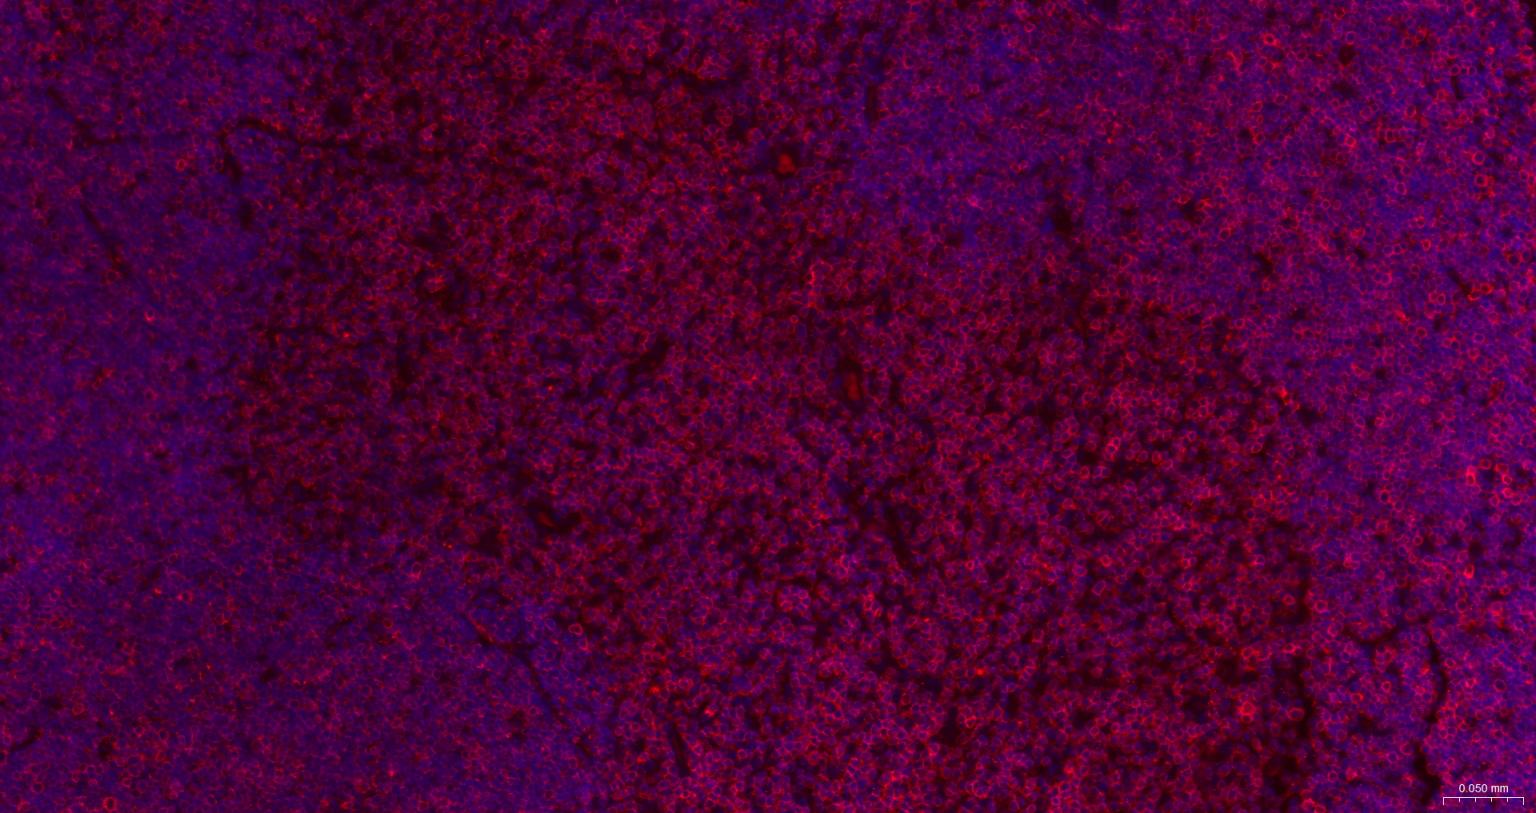

Paraformaldehyde-fixed, paraffin embedded Mouse Thymus; Antigen retrieval by boiling in sodium citrate buffer (pH6.0) for 15 min; The section was incubated with CD3E Monoclonal Antibody, Unconjugated (bsm-60002) at 1:500 overnight at 4°C. Followed by conjugated Goat Anti-Rabbit IgG antibody (Red, bs-0295G-BF594), DAPI (blue, C02-04002) was used to stain the cell nuclei.

Paraformaldehyde-fixed, paraffin embedded Rat Thymus; Antigen retrieval by boiling in sodium citrate buffer (pH6.0) for 15 min; The section was incubated with CD3E Monoclonal Antibody, Unconjugated (bsm-60002) at 1:500 overnight at 4°C. Followed by conjugated Goat Anti-Rabbit IgG antibody (Red, bs-0295G-BF594), DAPI (blue, C02-04002) was used to stain the cell nuclei.